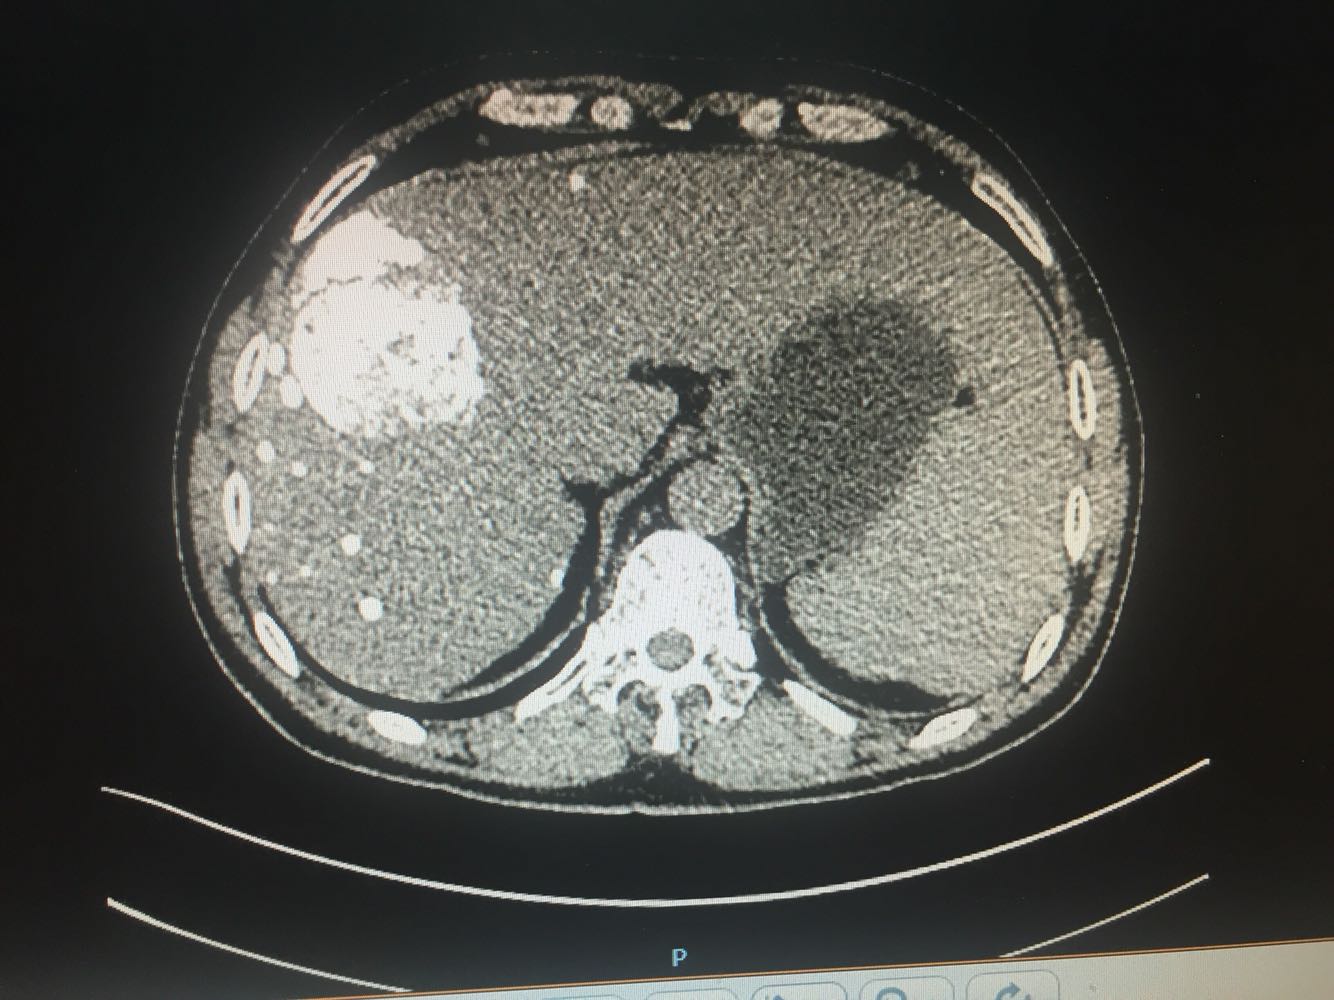

查体:体温,36摄氏度,脉搏:60次/分,呼吸,19次/分、血压,115/70mmhg,发育正常,营养欠佳,皮肤黏膜,色泽正常,双侧眼睑正常,双侧巩膜无黄染,口唇红润,双肺呼吸音清晰,心率60次/分,心律齐,心音有力,无病理性杂音。右上腹部饱满,中上腹压痛明显,肝脏肋下2cm触及,质地硬,触痛阳性,脾肋下2cm触及,移动性浊音阴性,肠音正常,双下肢无水肿 化验:血常规:白细胞计数2.9*10~9/L,中性粒细胞1.4*10~9L,红细胞计数4.03*10^12L,血小板计数76*10^9/L;生化全套。血糖4.67mol/L,总蛋白81.0g/L,白蛋白40.9g/1L,丙氯酸氨基转移酶256U/L,天门冬氨酸氨基转移酶182U,总胆红素22.0umol/L,胆碱酯酶4479U/L,Y-谷氨酰基转移酶137U/L;传染病9项:乙型肝炎病表面抗原阳性/6380,乙型肝炎病毒e抗体阳性/0.004,乙型肝炎病毒核心抗体阳性/0.008 肿瘤标志物:甲胎蛋白415.50ng/ml,乙型肝炎病毒DNA测定2.06E+07IU/ml CT:1.考虑肝右叶巨块型肝癌伴肝内多发转移,2.肝门部及腹膜后、心隔角旁小淋巴结。3.肝小囊肿。4.肝左叶増大。5.肝脏钙化灶。6.副牌。7.双肾微小囊肿

乙肝肝硬化,原发性肝癌,保肝抗病毒治疗,及TACE

出院一月后复查,行增强CT扫描,肿瘤明显缩小,肝功能正常,乙肝病毒复制转阴,建议继续口服恩替卡韦抗病毒治疗